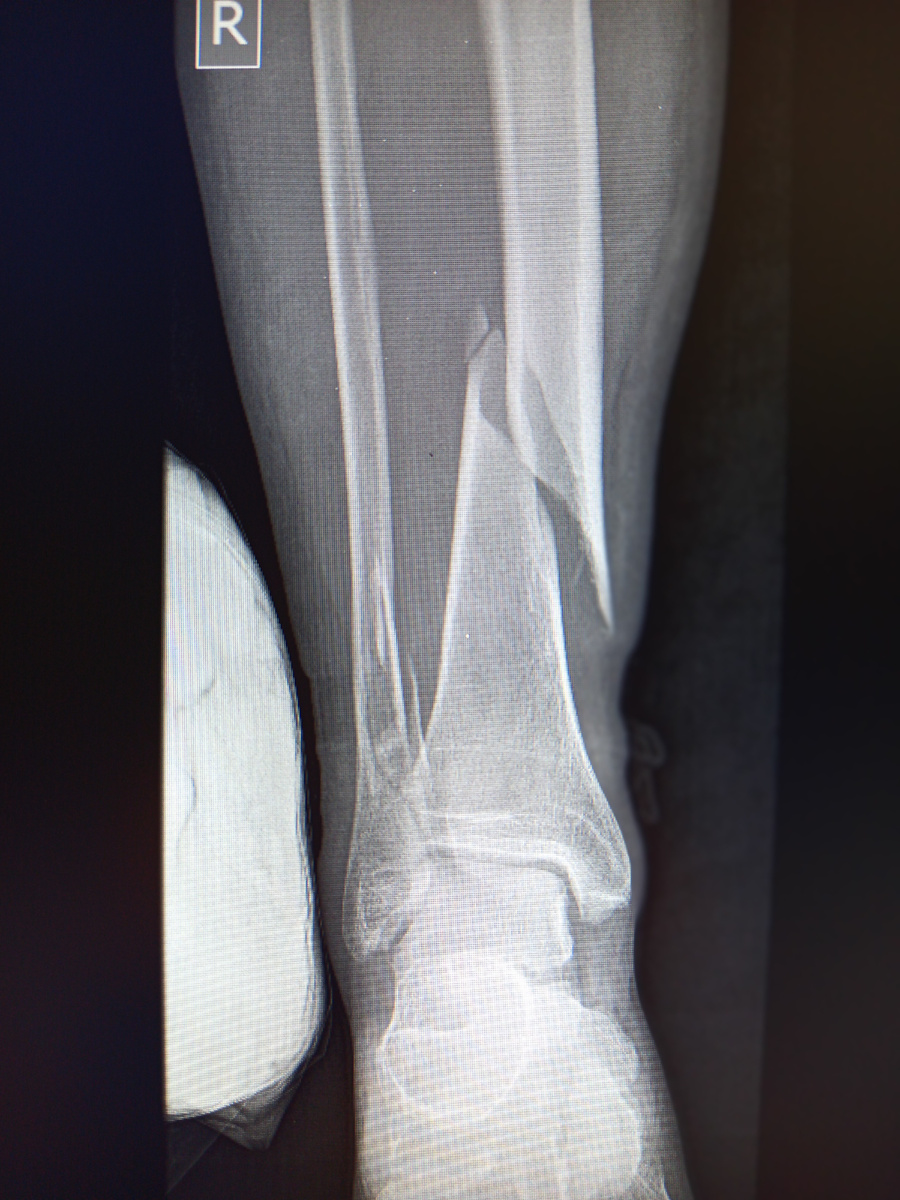

Уже ближе к ночи завезли каталку. Очень нетрезвый пациент , для которого возвращение с корпоратива закончилось падением на льду и переломом конечности.

Такое не перебинтуешь